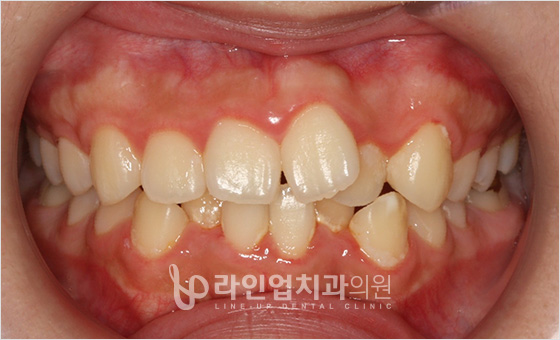

전후사진

치료전 Before

치료후 After